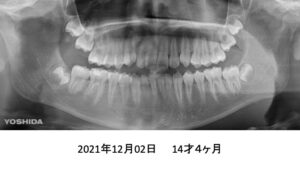

8歳の時、I市の歯科医院で、顎が狭くて歯が入りきらない、顎を拡げなければいけないといわれ、治療を開始したそうですが、6年経っても治療が終わらないどころか、写真のように全く噛み合っていないために、14歳の時にセカンドオピニオンで ひろ矯正歯科に来られました。

臼歯関係は、右が 4㎜ II級。左が 7㎜ II級で、7番しか咬合しておらず、著しい開咬を呈していました。